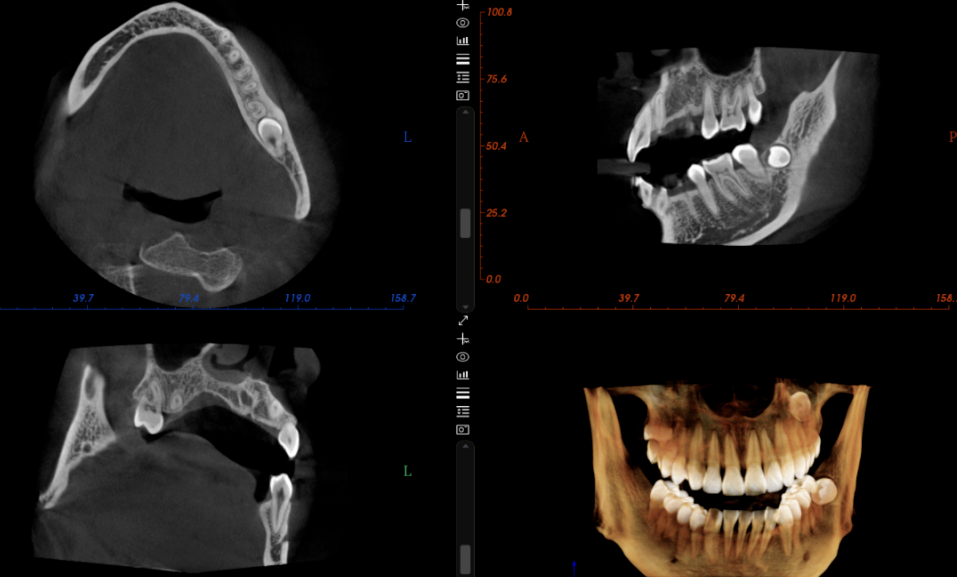

因為CT技術解決了傳統口腔X射線設備如口內牙片機和全景機所存在的圖像重疊和畸變問題。通過360°全方位立體觀測牙床的骨密度、牙槽骨的高度和寬度等數據,不僅可以完整重建顱面區域的結構,還能夠精確測量頜面骨骼結構,並還原細緻的解剖細節。

種植牙醫生可以借助CT機精確判斷全口牙床的位置、牙槽骨的高度和深度等資訊。這使得醫生能夠在電腦上清晰地分析牙槽骨的狀態,並在電腦上預先規劃種植手術,選擇適當的種植體,確定最佳的種植位置和角度。這進一步幫助醫生製作精准的手術範本,從而使種植牙手術更加安全可靠。